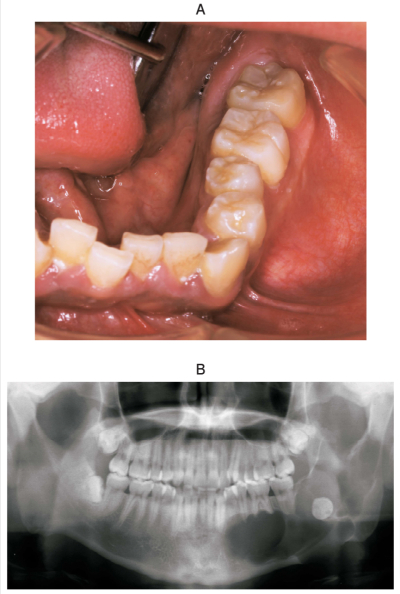

21 歳の男性。下顎左側部の腫脹を主訴として来院した。6か月前に気付き、徐々に増大してきたという。腫脹部に羊皮紙様感を触知する。検査の結果、開窓術を行うこととした。初診時の口腔内写真、エックス線画像、CT及び生検時の H-E 染色病理組織像を別に示す。